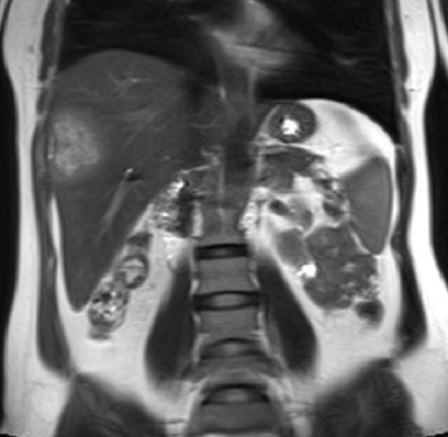

Image IRM du

carcinome hepatocellulaire : Image du masse a

iso ou hyposignal en T1 et hypersignal en T2 . Rehaussement

au temps arteriel et " wash out " au temps portal .

Image IRM enT1 du

carcinome hepatocellulaire : Aspect lesionaire

est isointense du foie droit ( fleche rouge ) . Foie

est en cirrhose , ascitique |

|

Image d'une carcinome

hepatocellule du foie droit en aspect une masse

nodulaire , hypersignale . Foie est en

cirrhose et ascite . Image IRM en T2 |